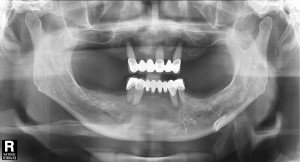

파노라마 방사선 사진도 살펴보면 치아를 잡는 치조골이 치아 뿌리 끝까지 많이 녹았음 확인할 수 있었습니다.

따라서 치아를 발치하고 전악 임플란트를 수복하기로 결정 하였습니다.